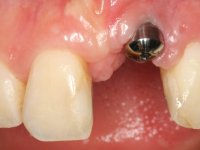

In the initial phase, it was proposed to the patient to perform the surgical implant exposure and after clinical evaluation, make prosthetic decisions. Once the healing screw was placed and the soft tissues were healed, an inadequate position of the implant was found. In view of the dramatic situation, the patient was proposed to remove the implant and put a new one after tissue regeneration. This proposal was rejected by the patient, who suggested temporary rehabilitation of the current implant. A new proposal was then made, to rehabilitate the implant, consisting of a screwed abutment, and on this, the placement of an acrylic crown with coronal and gingival components. After 6 years with the provisional treatment, the patient appeared in consultation with an abscess in tooth 1.1. After clinical and imaging analysis, it was decided to remove teeth 1.1 and 2.2, submerge the implant, place two implants at the site of 1.1 and 2.2 and perform adequate tissue regeneration. Temporization would be done with a provisional 3-element bridge, adhered with a net to the neighboring teeth. After osseointegration, definitive rehabilitation would be done with a 3-element bridge, including zirconia infrastructure and ceramic cover.

The surgical implant exposure and the healing screw placement proved to be a negative surprise regarding its position. Since the proposed removal of the implant was refused, we advanced to its provisional rehabilitation. An open tray impression technique was done, and a screwed abutment with a coronal and gingival component and an acrylic crown were made in the laboratory, using these two components. The provisional crown was placed in the mouth until a final decision was made. Six years passed before the patient returned to the clinic with an abscess on tooth 1.1. The choice to remove teeth 1.1 and 2.2 was made, to create a provisional 3-element bridge with a net to be adhered to the adjacent teeth. Surgery was planned and performed, placing the two implants at the site of 1.1 and 2.2, and the implant at the 2.1 site was cut with the objective of submerging it, while adequate tissue regeneration was performed (Surgical Work performed By Dr. Manuel Neves). During osseointegration, the patient used the fixed provisional bridge. A first impression was made for confection of a zirconia screwed provisional bridge, which worked the soft tissues for twelve weeks. The definitive impression was made with the individualisation of custom impression copings. Final rehabilitation was done with ceramized abutments, and also a bridge with zirconia infrastructure and ceramic cover. Due to the inclination of the implant placed at the site of tooth 1.1, the bridge required cemented fixation.